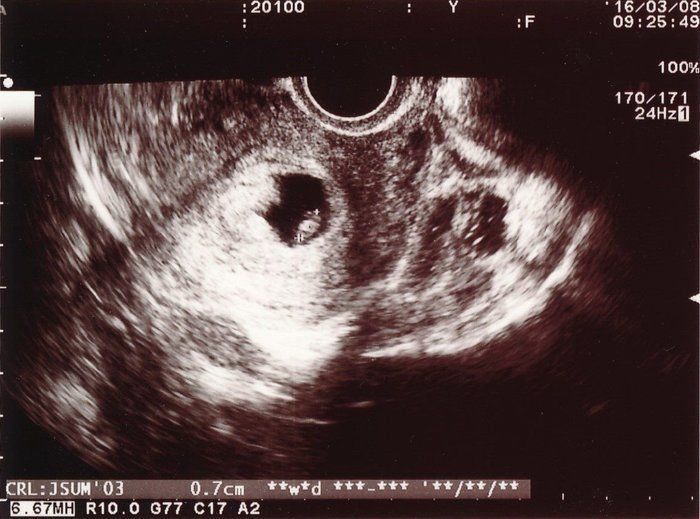

小吉さんの妊娠6週目のエコー写真

待ちに待った診察の日です。自分の中では妊娠していると確信がありましたが、医師のお墨付きをもらわなければなりません。先週よりも大きくなった胎嚢の中に赤ちゃんの姿が見えます。このときは0.7cmですが、心音が確認できたことが決め手となり妊娠が確定しました。しかし、妊娠初期での流産リスクは25%と告げられ、落ち込む暇もなくどのようにして乗り切るかを考え始めました。